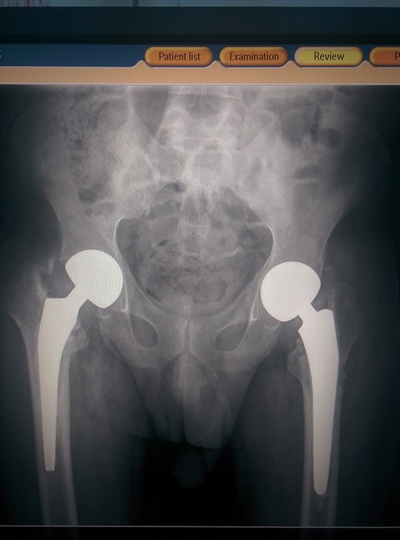

Когда железа больше чем костей. Чувствовала себя терминатором.